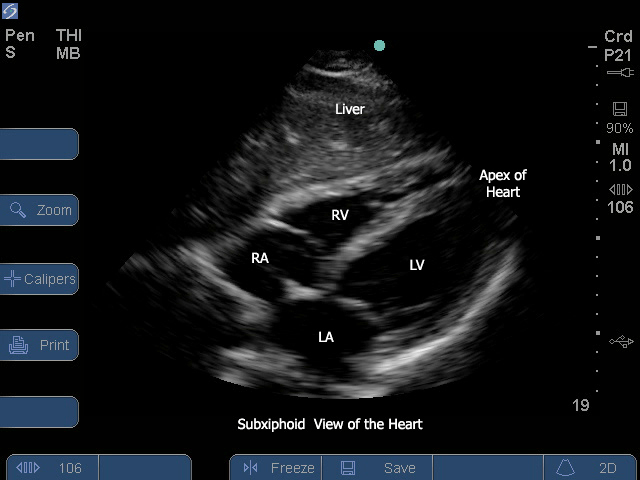

Sonosite subcostal view